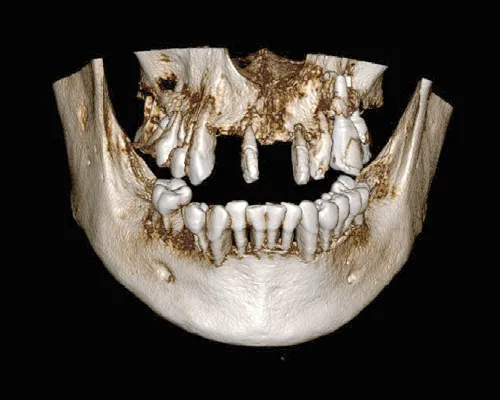

- ①各種検査

レントゲン検査(パノラマ、デンタル、CT、セファロ)

むし歯や歯周病の診査、咬み合わせの診査を行い、まずは骨の状態や歯肉の状態を正確に診断します。

STEP1

- 3次元CTで撮影

- 骨質、神経の位置などを分析・診断